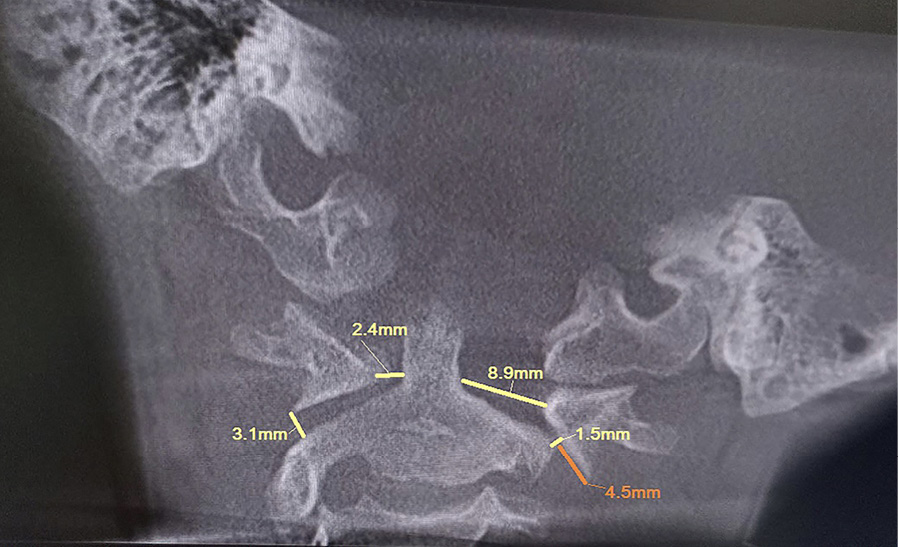

Клиническое наблюдение 1

Рис. 1. Конусно-лучевая компьютерная томография краниовертебральной области, фронтальный срез на уровне зубовидного отростка С2 позвонка. Методика измерения соотношений в латеральных атланто-аксиальных суставах